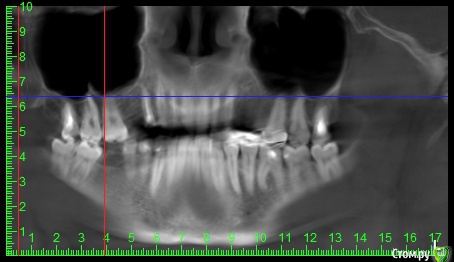

alex889 Опубликовано 8 февраля, 2020 Поделиться Опубликовано 8 февраля, 2020 Подскажите, над предпоследним зубом сверху это инородное тело в гайморовой пазухе? Это могло попасть при лечении каналов зуба мудрости? Может ли такое инородное тело вызывать боли и воспаление в челюстно-лицевой области?Файл КТ: http://fayloobmennik.cloud/7384939 Ссылка на комментарий

wladdX Опубликовано 10 февраля, 2020 Поделиться Опубликовано 10 февраля, 2020 (изменено) Инородных тел не нашёл. То что Вы приняли за инородное тело - перегородка в пазухе Изменено 10 февраля, 2020 пользователем wladdX 1 Ссылка на комментарий